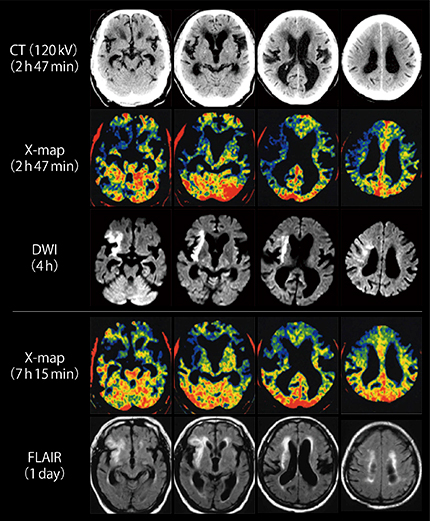

図6は,急性期脳梗塞における発症後約3時間からの経時的画像である。発症3時間後のX-mapにて広範囲に青く描出された領域が,血栓回収術施行後の発症約7時間後のものでは縮小している。通常のCT画像ではとらえられないCT値の何らかの変化,例えば機能・代謝のダイナミックな変化をX-mapがとらえている可能性がある1)。しかしながら,アーチファクトをとらえている可能性を完全には否定できないことと,理論的にもY軸の変化の方が優位である病変の検出が困難となることから,通常のCTを置き換えることはできず,X-mapはあくまでもサポート画像の位置づけである。

図6 急性期脳梗塞における経時的な画像比較